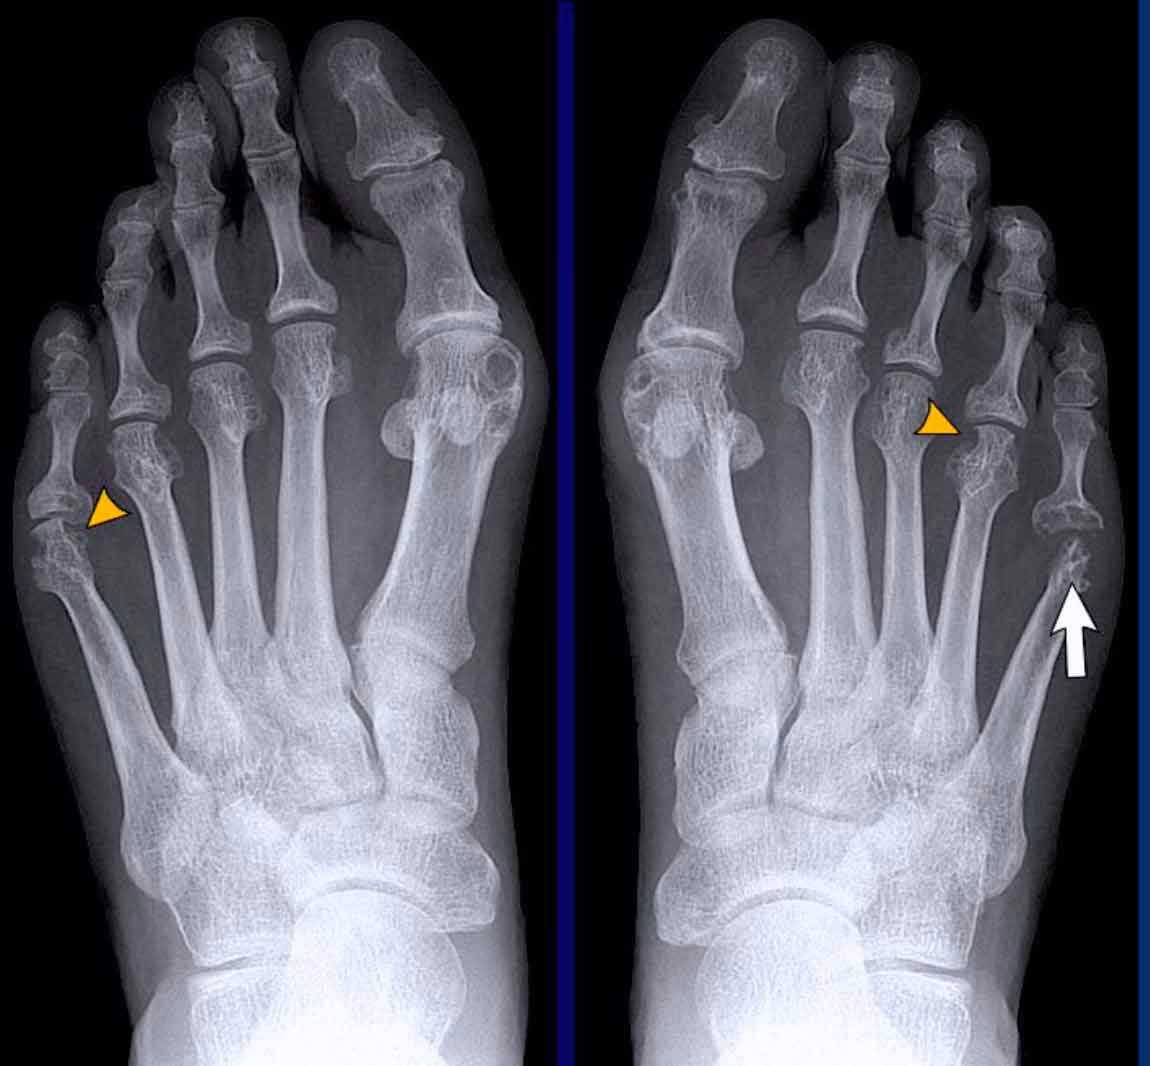

Udfordringerne ved Traditionel Diagnostik: Vægtbærende Røntgen

I årtier har vægtbærende almindelige røntgenbilleder været den primære metode til at diagnosticere knogle- og ledproblemer i foden. 'Vægtbærende' betyder, at billederne tages, mens patienten står op, så lægen kan se, hvordan knoglerne og leddene opfører sig under kroppens vægt. Dette er især vigtigt i foden, da mange problemer kun bliver tydelige under belastning.

På trods af dens udbredte anvendelse har vægtbærende røntgen betydelige begrænsninger, når det kommer til mellemfodsartrose:

- Overlejring af knogler: Mellemfoden er en tredimensionel struktur med mange små knogler, der ligger tæt på hinanden. På et todimensionelt røntgenbillede overlapper disse knogler hinanden, hvilket gør det ekstremt svært at få et klart billede af de enkelte ledspalter. Det kan være næsten umuligt at vurdere, om der er en indsnævring af ledspalten, hvilket er et kardinaltegn på artrose.

- Lav sensitivitet for tidlige stadier: I de tidlige stadier af artrose er forandringerne ofte subtile. Røntgenbilleder er ikke altid følsomme nok til at opfange den tidlige nedbrydning af brusk eller små osteofytter. Dette kan føre til en forsinket diagnose, hvor patientens symptomer fortsætter, selvom røntgenbilledet ser normalt ud.

- Begrænset information: Et røntgenbillede giver primært information om knoglerne. Det giver begrænset indsigt i det omkringliggende bløddelsvæv, såsom ledbånd og sener, som også kan være påvirket.

Disse begrænsninger betyder, at den diagnostiske sensitivitet (evnen til korrekt at identificere dem med sygdommen) og specificitet (evnen til korrekt at identificere dem uden sygdommen) for røntgen kan være utilstrækkelig i komplekse tilfælde.

Direkte Sammenligning: Røntgen vs. CT-Scanning

For at give et klart overblik over forskellene mellem de to metoder, kan vi opstille en sammenligningstabel. Studier, der har undersøgt den diagnostiske nøjagtighed, har generelt vist, at vægtbærende CT-scanning har en højere sensitivitet og specificitet til at identificere artrose i specifikke led i mellemfoden sammenlignet med almindelig røntgen.